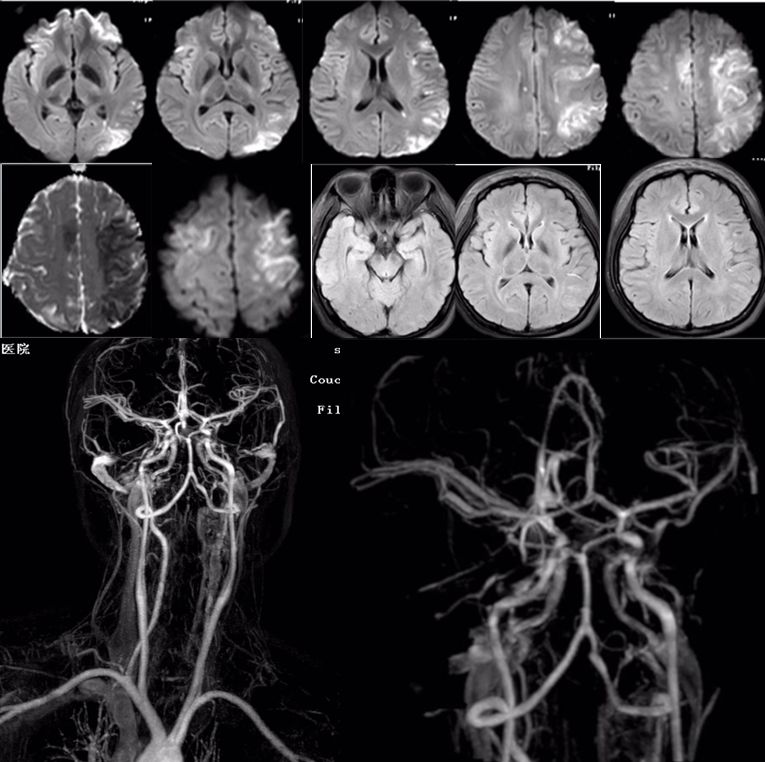

男,29岁,言语不清,协调不良以及行走不平衡3周。

答案:*洛因海**海绵状白质脑病。*洛因海**海绵状白质脑病(heroin spongiform leukoencephalopathy,HSLE)是因烫吸或静脉注射*洛因海**而引起的中枢神经系统器质性疾病。临床和影像特点如下:

1. 有吸*洛因海**史;

2. 急性或亚急性起病;

3. 小脑受损为首发症状,进一步加重可出现锥体系及锥体外系受损表现,甚至昏迷、去皮层状态,但感觉系统不受累;

4. CT和MRI影像显示病灶位于脑白质区,呈广泛、对侧性损害(小脑半球、脑干、内囊后肢、胼胝体压部及大脑半球后2/3),其中小脑受累严重,小脑中线两旁、边界清楚的对侧性类圆形或蝴蝶样病灶最具特点(蝶翼征);在脑干部位,若同时有红核及网状结构受累,则可见“蟹钳征”;在内囊后肢则呈“八字征”。病变在T1W为低信号,T2WI为高信号,FLAIR为高信号,且增强扫描一般无强化.5.病理显示脑白质空泡样变。

30岁女性,言语不清3年。

答案:肝豆状核变性。又称Wilson’病(WD),是一种常染色体隐性遗传的铜代谢障碍性疾病。主要是由于铜离子异常大量沉积于肝、脑、肾等组织,从而导致全身多系统多器官的损害,以神经系统症状、精神症状、眼部损害、肝脏损害等为主。神经系统最突出的症状是锥体外系症状,包括震颤、构音障碍、肌张力障碍、手足徐动症、共济失调等。构音障碍表现为声音低沉、含糊或嘶哑、缓慢或断续,严重时发不出声,是舌、唇、咽、喉和下颌肌肌张力增高所致。而肝脏的表现通常为肝功能损害、肝硬化、门脉高压症等,一般年轻患者居多。MRI表现为壳核、尾状核头和苍白球在T2WI上呈低信号,齿状核和红核亦可见T2WI为低信号。还可有不同程度的脑萎缩,如两侧壳核对称性裂隙,豆状核、尾状核、大脑皮质、脑干和小脑的萎缩。大小熊猫征为Wilson病的典型特征。